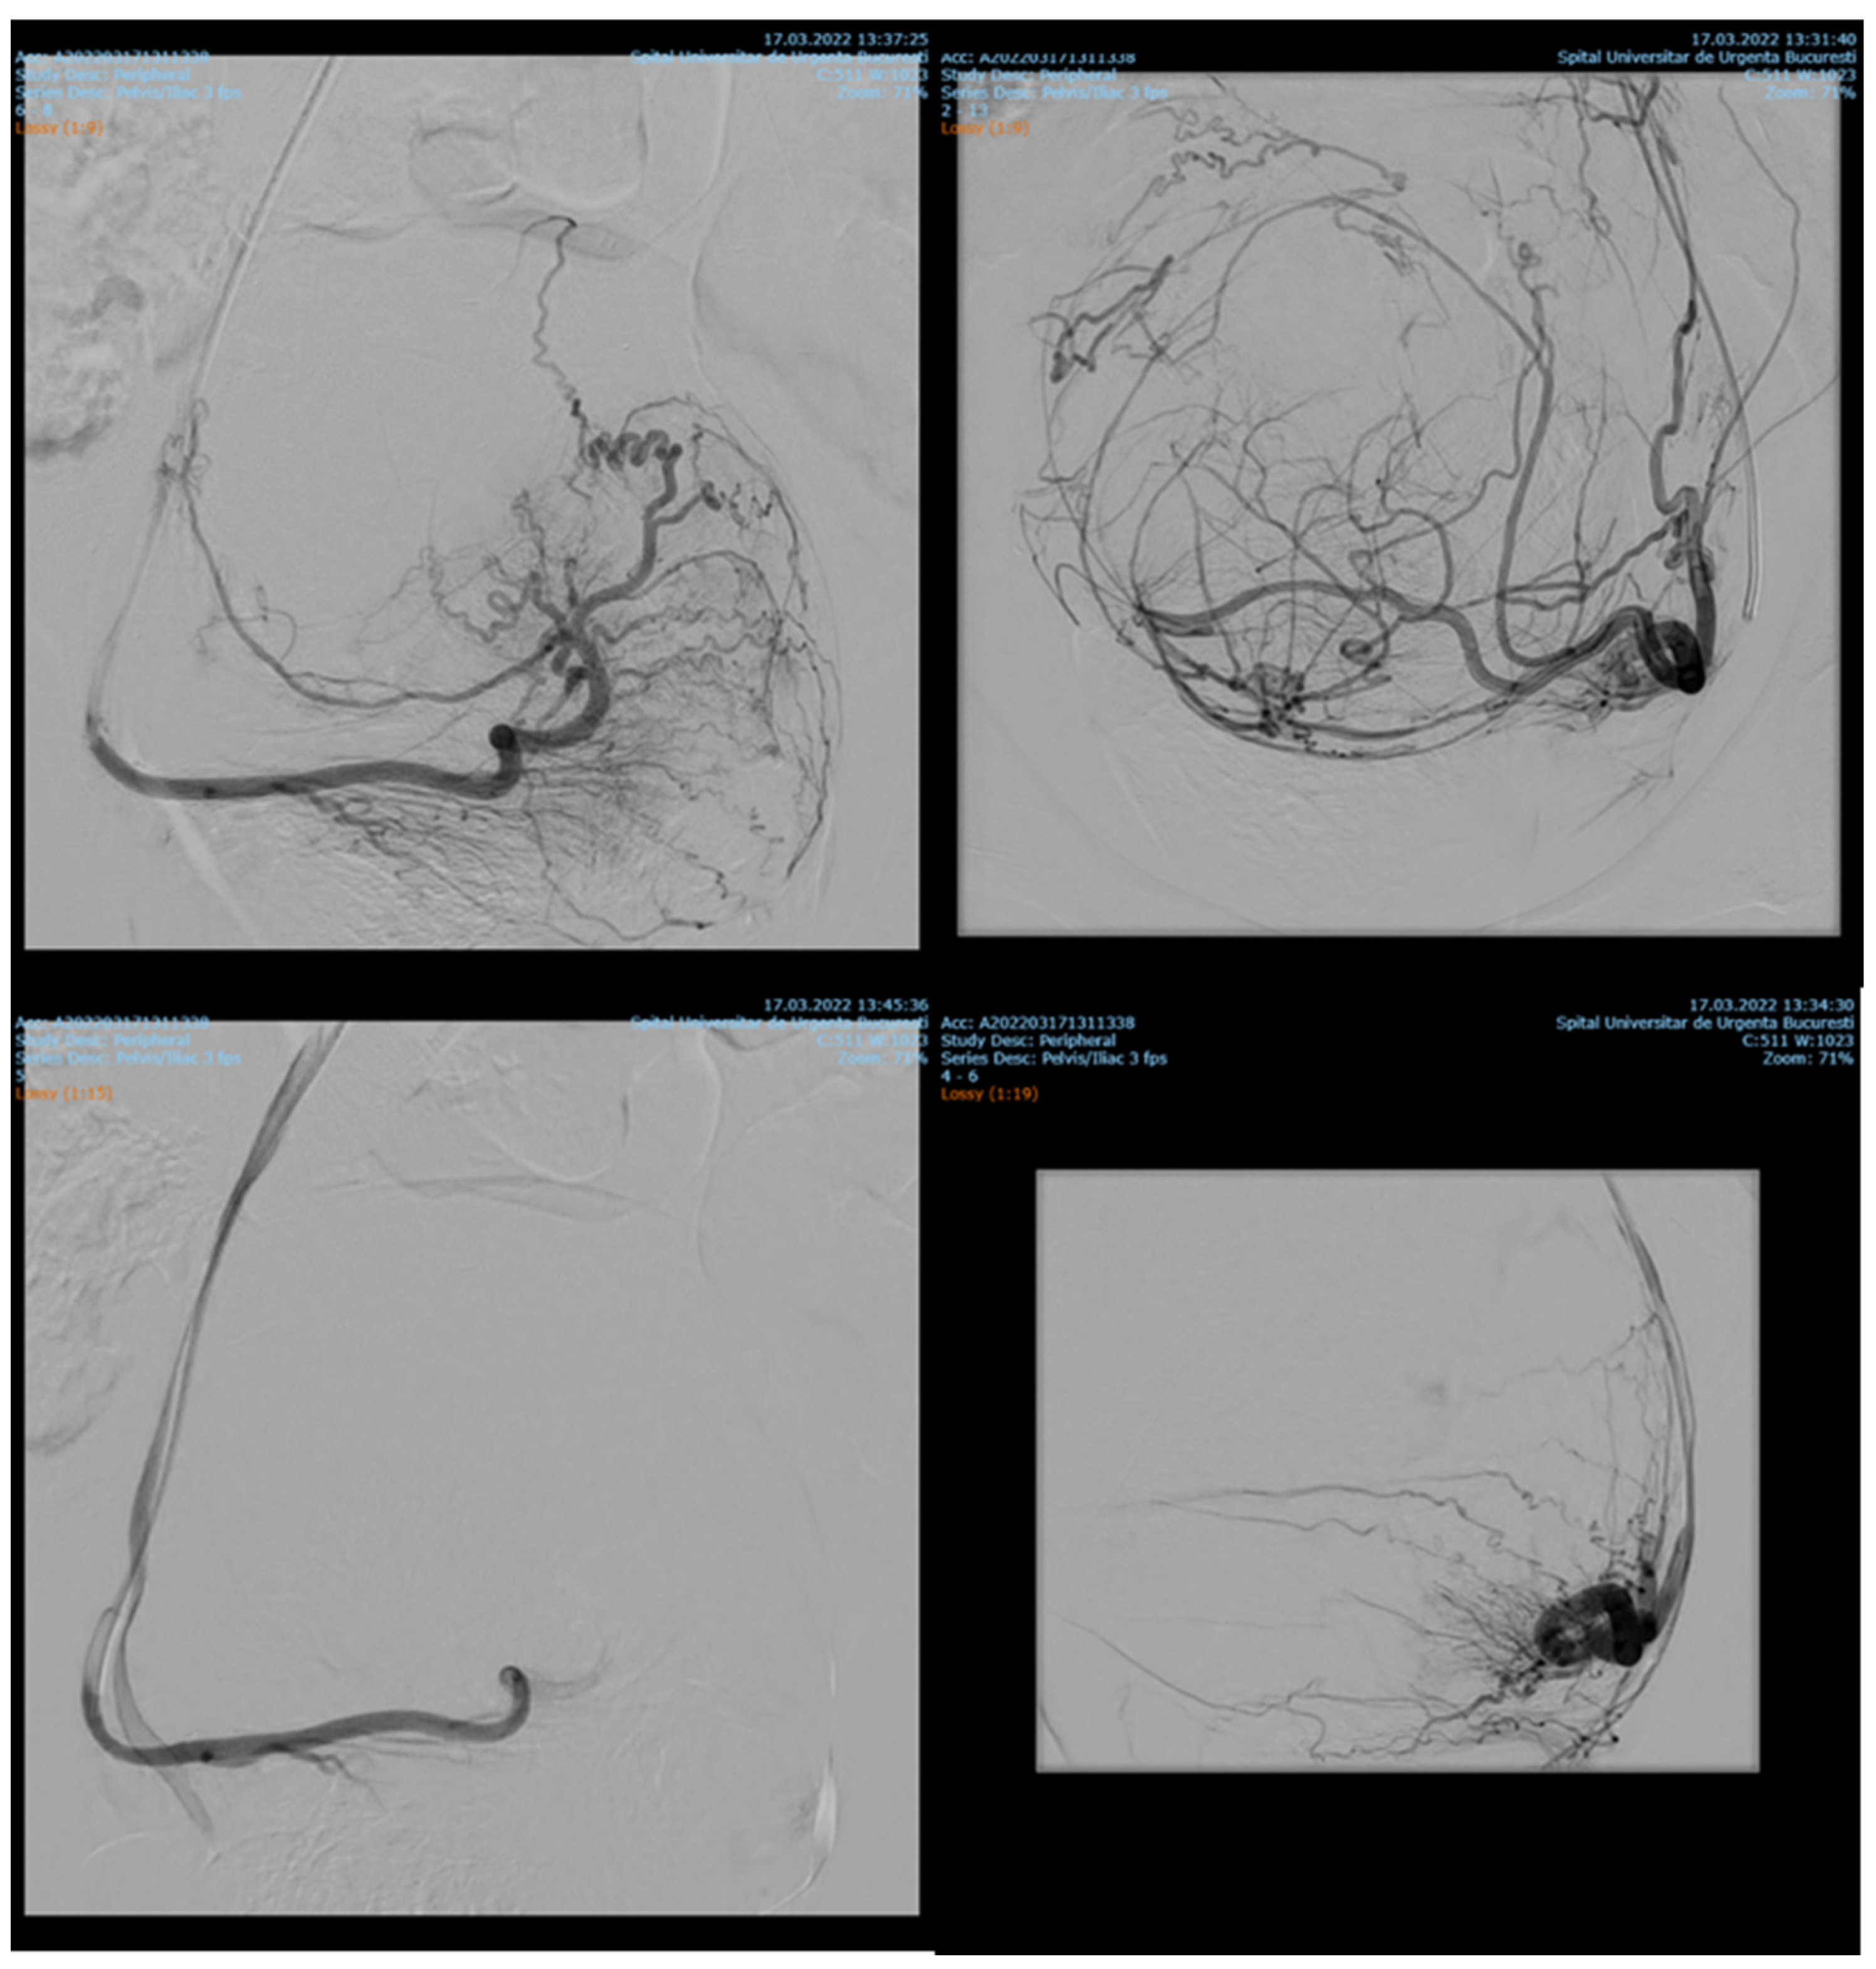

Endovascular procedures were used in 2.29% of cases with ectopic pregnancy (n = 26) (see Figure 4 and Figure 5), 1.23% of patients with arteriovenous malformation (n = 14) (see Figure 6), and 0.52% of patients with major hemorrhage of obstetrical causes (n = 6).

In 97% (n = 1101) of patients, bleeding was stopped after the first attempt of PAE. 3% (n = 34) needed a second embolization. In 12 of 14 cases of AVM, PAE was successful, but in the other two cases, reintervention was needed.

Studies conducted by Jacobowitz et al. and by Ghai et al. support the importance of embolization procedures in bleeding caused by AVM, stating that in some of the cases, re-embolization or even hysterectomy might be needed [2,23,24]. In our study, none of the patients needed hysterectomy, but in two cases we had to reintervene and perform another embolization. Barral et al. concluded that PAE in patients with AVM is effective and does not affect fertility. During the study, they used ethylene vinyl alcohol copolymer [25]. In all our 14 patients with AVM, we used gel-foam, peripherical coils and closure devices.

Figure 6. Selective artery embolization in patient with arterial venous malformation.